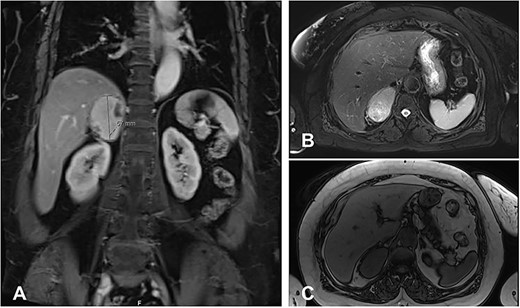

An MRI revealed a right adrenal mass with an avid enhancement of central cystic changes, and the mass was abutting the medial border of segments 8 and 7 of the liver without invasion (Fig. 1). The final impression was an incidental nonfunctional right adrenal mass with a clinical and radiological characteristic of pheochromocytoma.

MRI Abdomen with and without IV contrast. Right adrenal mass demonstrating high T2 and low T1, with cystic changes. (A), an axial T2 weighted MRI shows a hyperintense right adrenal mass with cystic changes, abutting the liver without invasion. (B), a cross-section T2 weighted MRI shows a hyperintense large right adrenal mass. (C), cross-section T1 weighted MRI shows a large right adrenal mass characterized by hypointernse lesion compared with hepatic parenchyma.